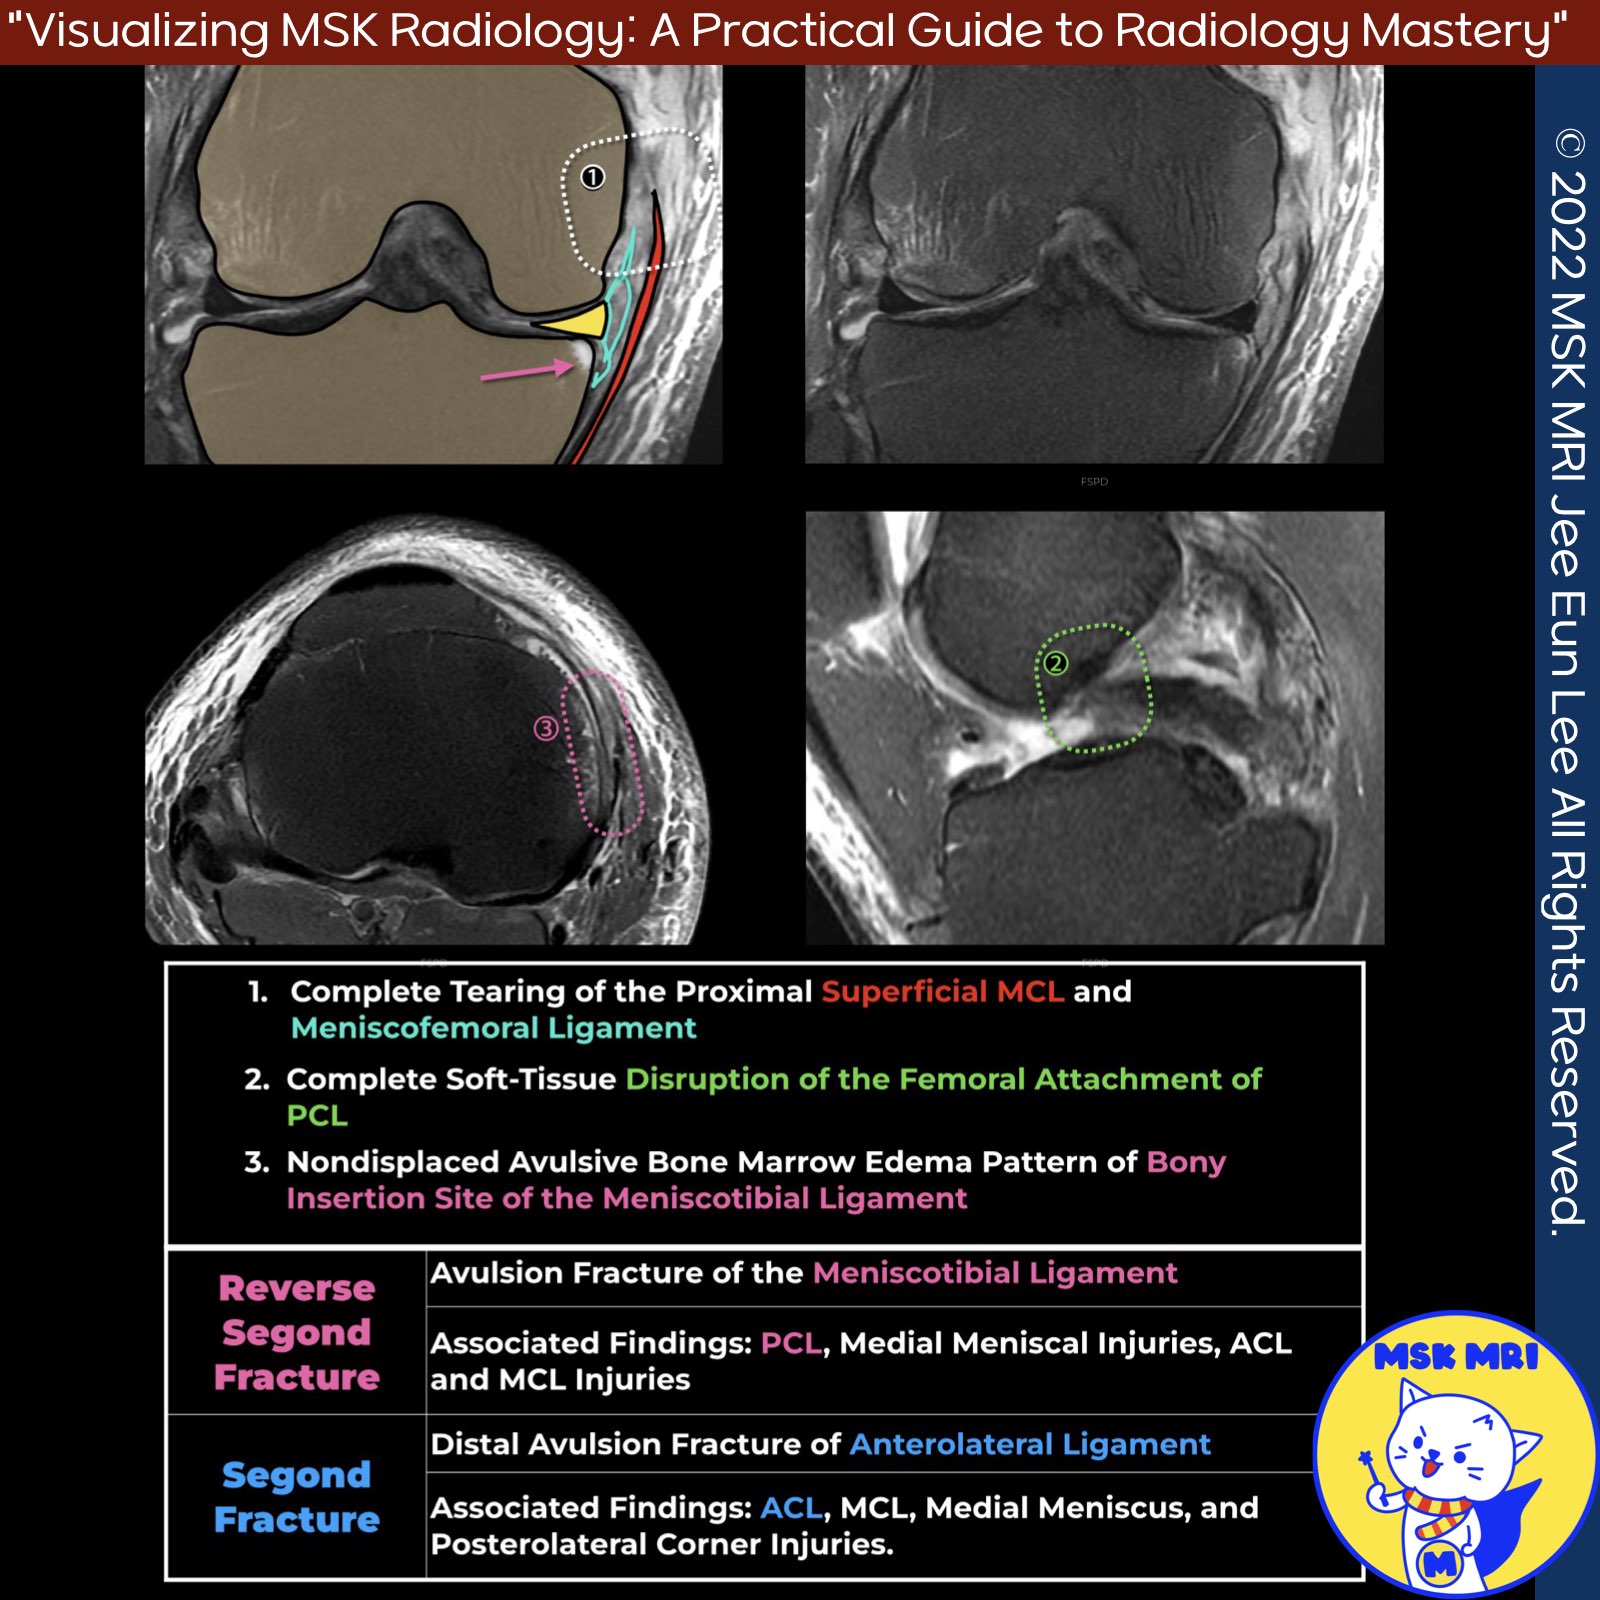

📌 Segond Fracture

- Avulsion fracture of anterolateral ligament at tibial insertion

- Associated with ACL, MCL, medial meniscus, posterolateral corner injuries

- Seen in around 40% of ACL injuries

- Indicates anterolateral rotatory instability

- Commonly occurs with sporting injuries

📌 Reverse Segond Fracture

- Avulsion of meniscotibial ligament at tibial insertion

- Associated with PCL, medial meniscus, ACL, MCL injuries

- Occurs with high-velocity trauma like motor vehicle collisions

- May be associated with knee dislocation